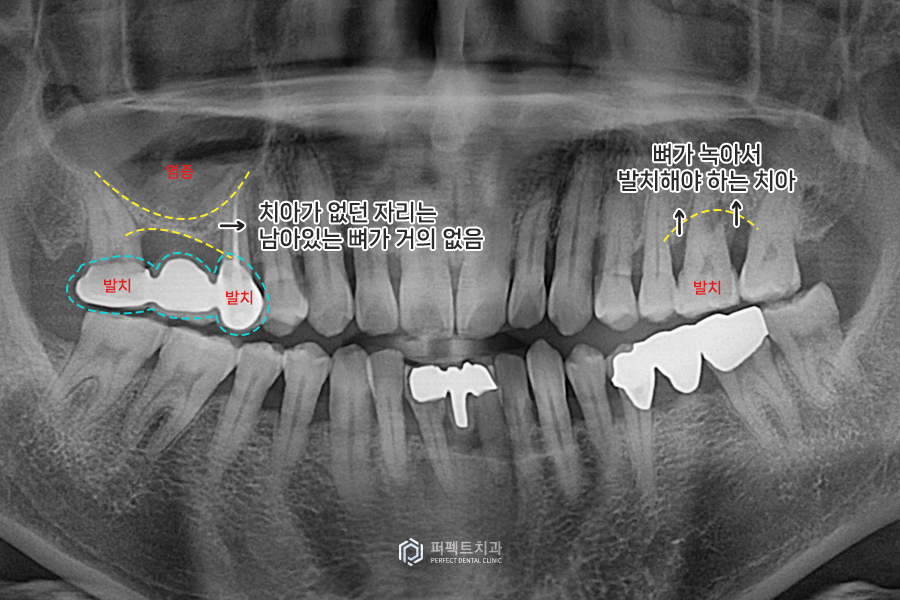

이 환자분은 왼쪽, 오른쪽 어금니가 아파서 오신 경우입니다. 보니까 왼쪽에 뼈가 녹아서 발치를 해야 하는 치아가 있고, 오른쪽에 있는 치아도 많이 아파하시는 상황이었습니다. 오른쪽 통증이 있는 치아는 예전에 '브릿지'라는 치료를 받고 오랫동안 사용하시고 있었는데, 이를 임플란트를 교체하기를 원하셨습니다.

통증이 있는 치아 부위는 상악동에 염증이 있고, 치아가 없던 자리(브릿지를 했던 자리)는 뼈가 거의 없는 상태입니다. 이 사진으로만 봐도 1~2mm정도 있을까 하는 정도인데 임플란트를 편안하게 심으려면 적어도 10mm길이의 공간이 있는 것이 좋습니다.